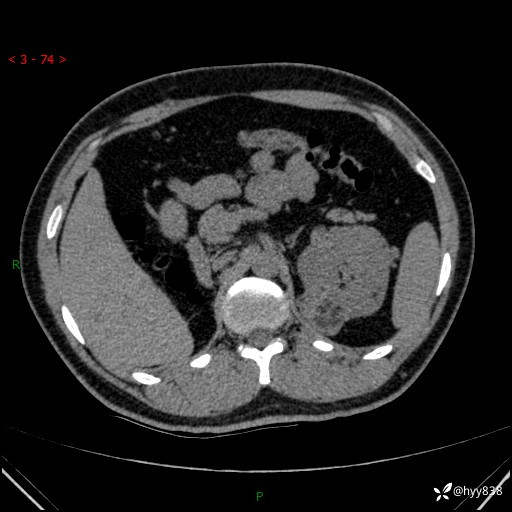

患者性别:男

患者年龄:28岁

简要病史:右肾肿瘤术后,常规复查

辅助检查:CT

临床诊断:右肾肿瘤术后

讨论:病变性质?

腹部CT+颅脑CT平扫